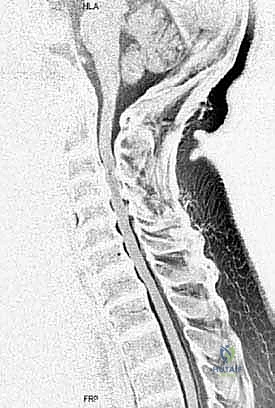

FIG 2 • B. Sagittal T2-weighted MRI showing multilevel cervical disc protrusions and circumferential stenosis at C3–4, C4–5, and C5–6, resulting in cord deformation. Cord signal changes can be seen at C3–4 and C4–5, indicative of cord damage.